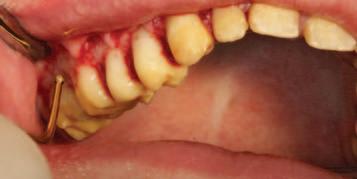

A unilateral sagittal split osteotomy was performed using piezosurgery to protect the nerve. The alveolar nerve, extending from the apical region of the left first and second molars to the mental foramen, was uncovered, and a meticulous dissection was performed to release it from the canal. Notably, rigid paste debris was observed in proximity to and within the nerve canal. The nerve exhibited signs of swelling and was surrounded by granulation tissue (Figures 4 and 5 ).

FIGURE 5: The root canal filling material being removed from the canal.